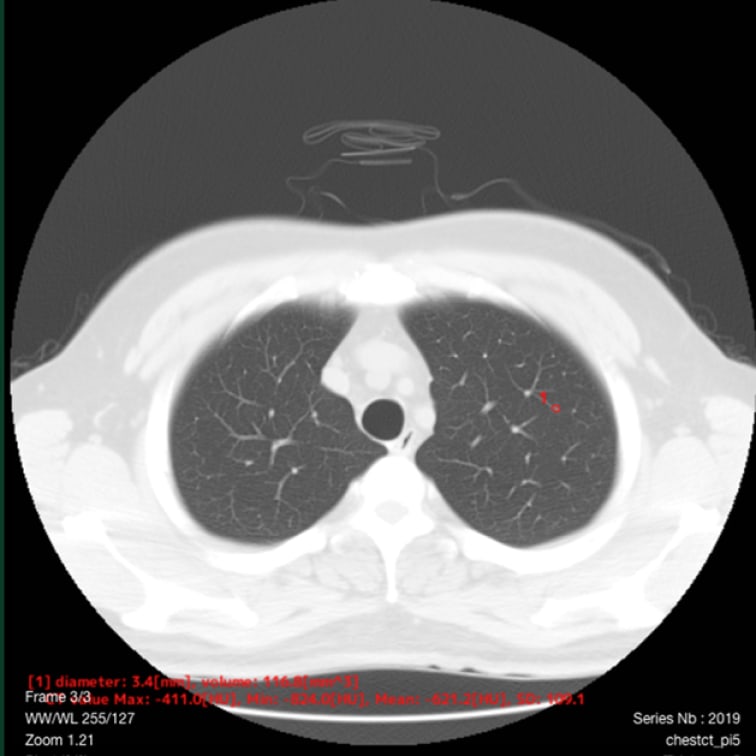

以下の肺結節候補領域を検出して表示します- 充実型:3mm以上30mm以下

- 部分充実型:5mm以上30mm以下

- すりガラス型:5mm以上30mm以下

- 自動計測

- 検出した候補領域の大きさ:体積 [mm³] およびAxial断面最大径 [mm] を出力

- CT値:最大・最小・平均値・標準偏差を出力

解析事例

標準線量CT